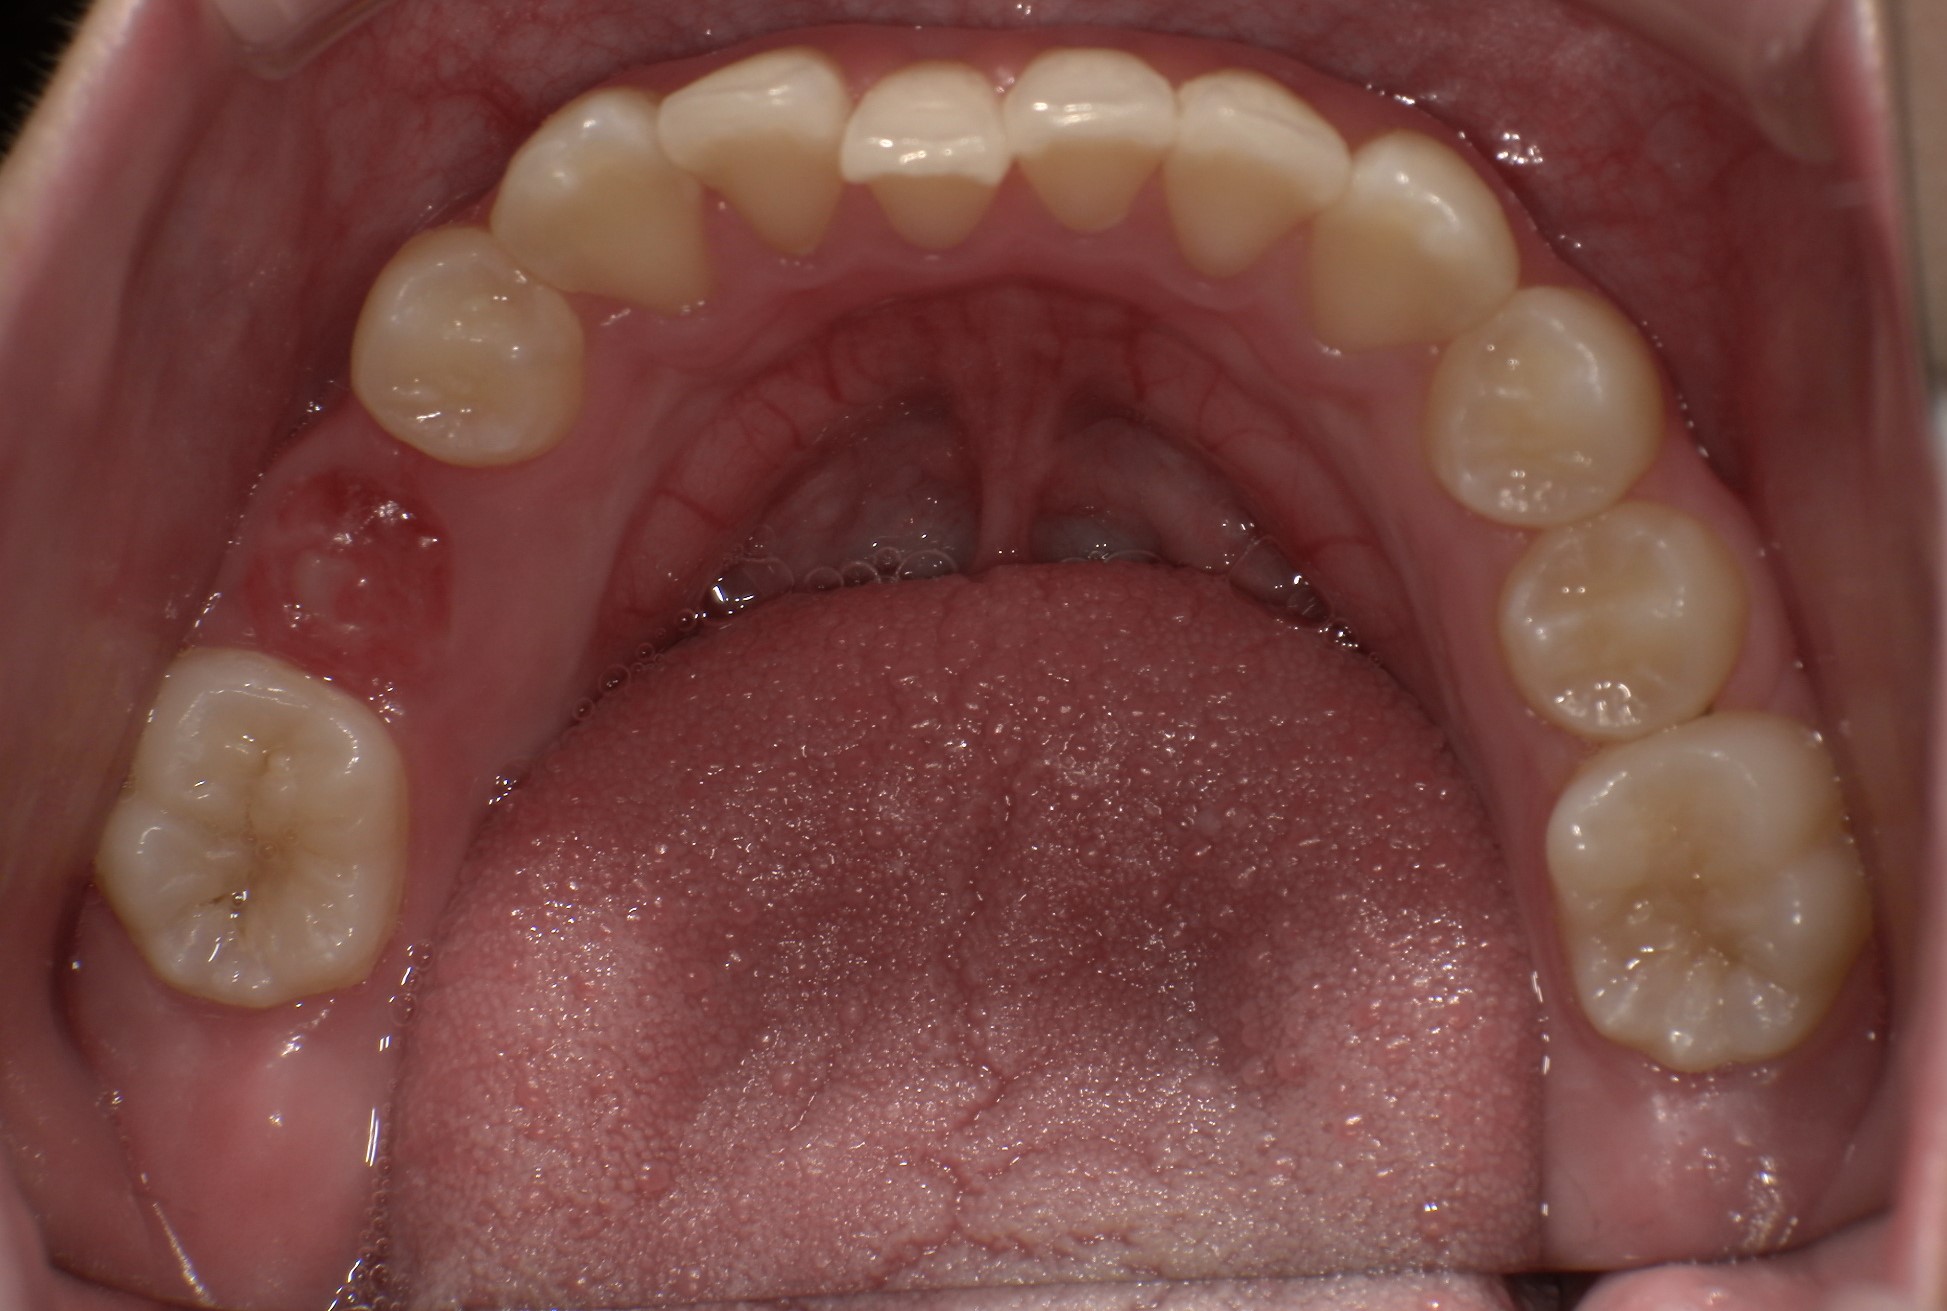

バイオネーターの症例

主訴 | 出っ歯が気になる |

---|---|

治療内容 | バイオネーター |

治療期間 | 1年11ヶ月 |

治療費用 | 330,000円(税込) |